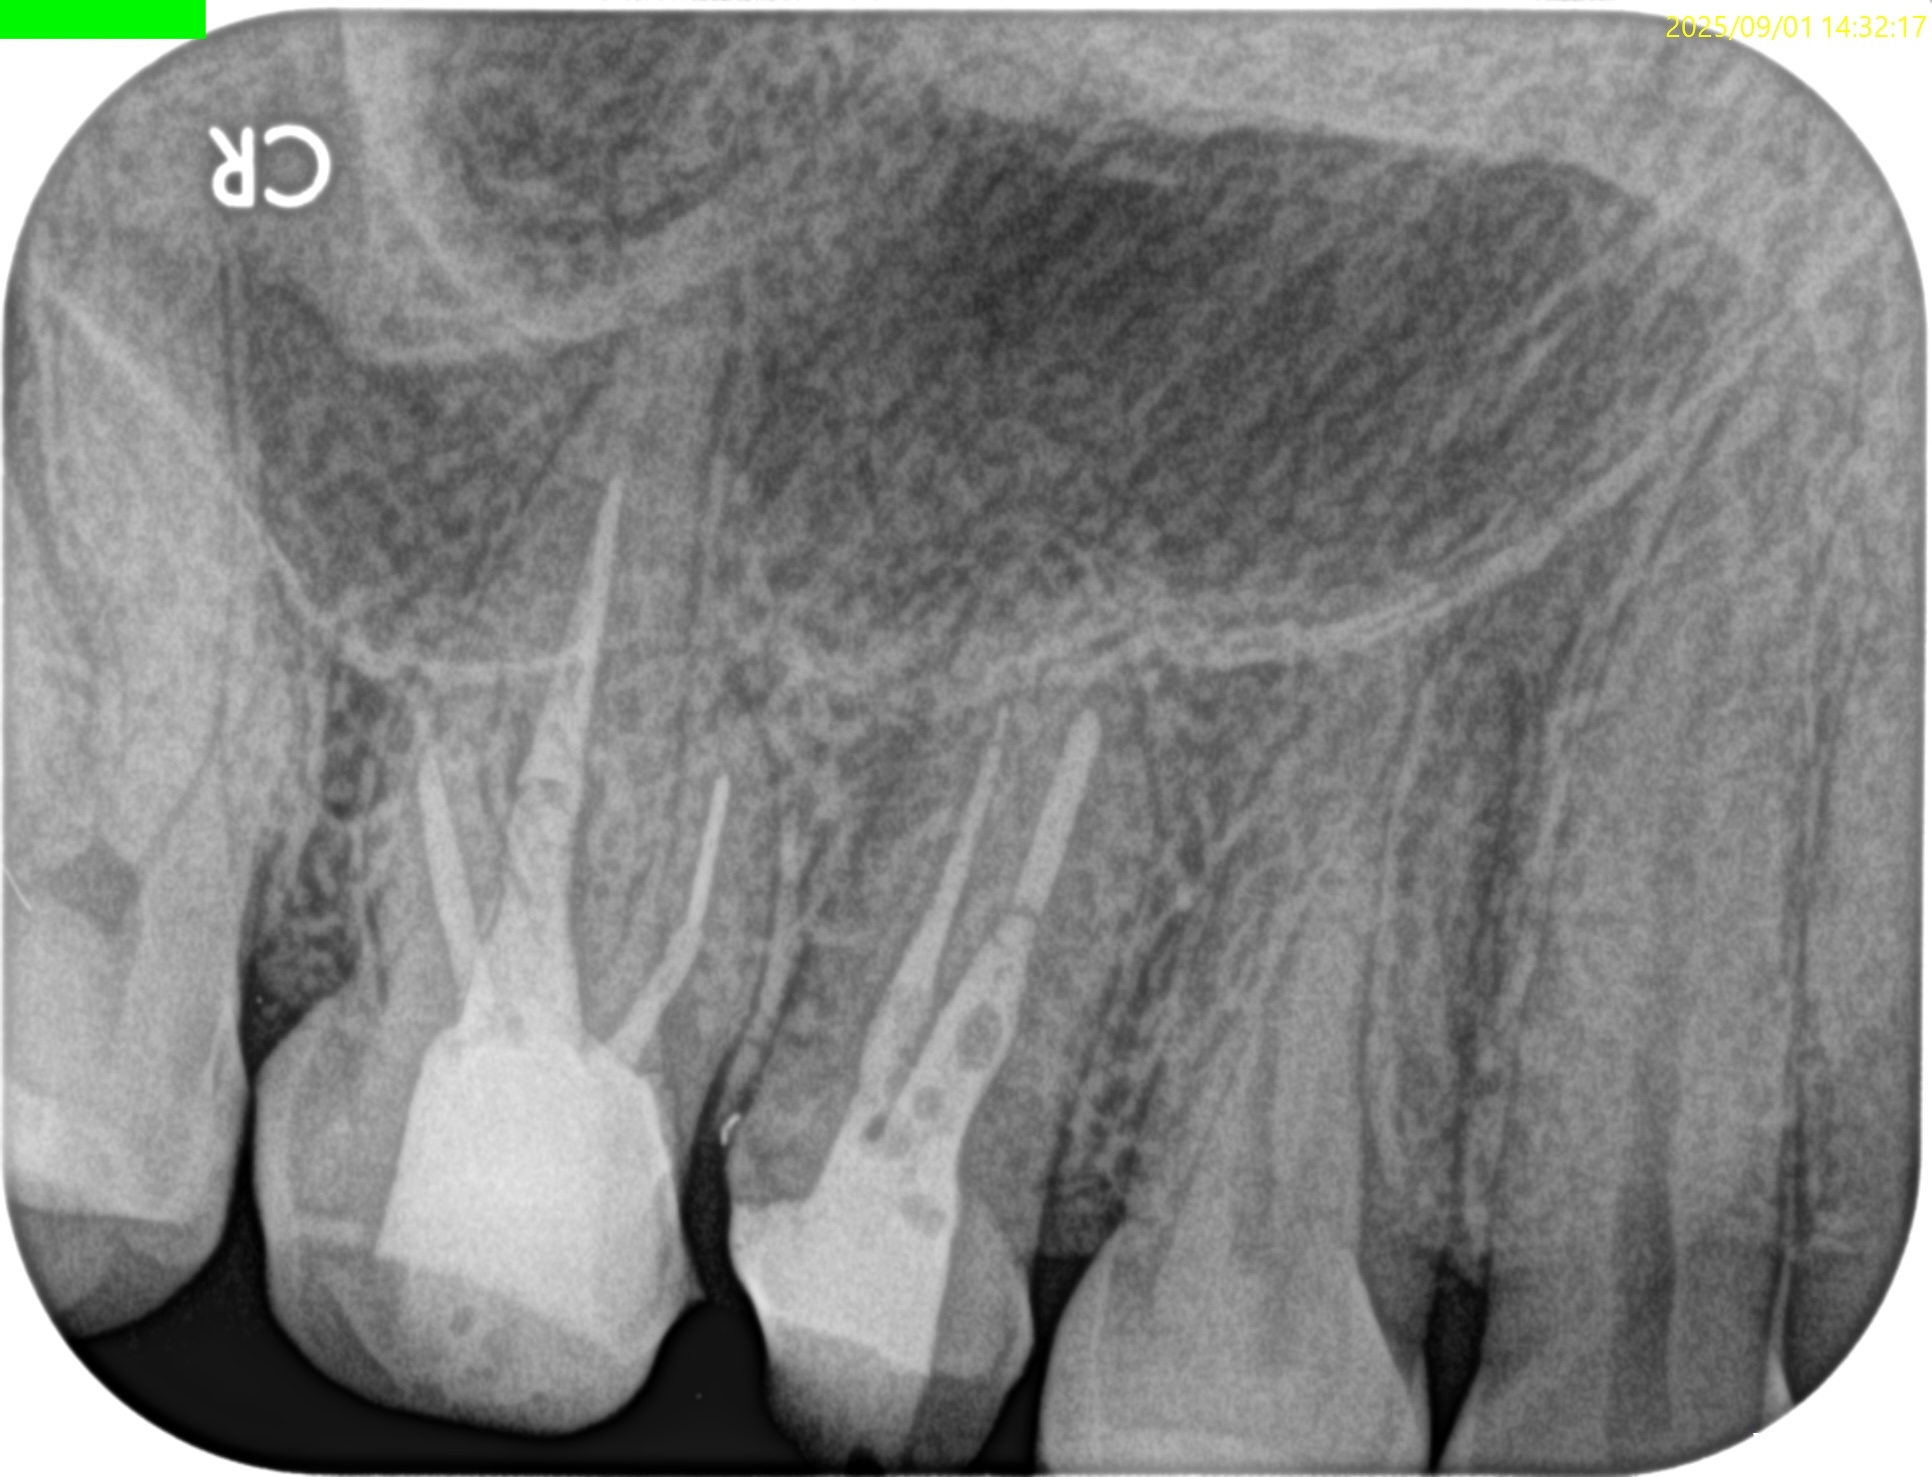

PA(2025.9.1)

#3

MB

DB

P

#4

B

#3のMBにはFileが折れ込んでいる。

#4はP根管が未着手だ。

#3に関してだが、MBの破折ファイルはちょうどカーブの変曲点を超えて根尖部に折れ込んでいる。

この時点で、それをいかにして除去するか?よりも、FileごとApicoectomyしたほうが時短になると私は考える。